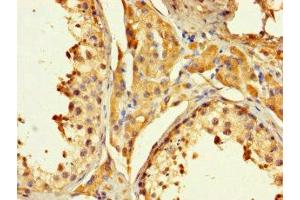

PAGE1 anticorps (AA 1-146)

Aperçu rapide pour PAGE1 anticorps (AA 1-146) (ABIN7162427)

- PAGE1 Antibody

- PAGE1 (P Antigen Family, Member 1 (Prostate Associated) (PAGE1))

Background: cellular defense response

Aliases: AL5 antibody, G antigen 9 antibody, G antigen family B member 1 antibody, GAGB1_HUMAN antibody, GAGE 9 antibody, GAGE-9 antibody, GAGE9 antibody, GAGEB1 antibody, P antigen family, member 1 (prostate associated) antibody, PAGE 1 antibody, PAGE-1 antibody, PAGE1 antibody, Prostate-associated gene 1 protein antibody